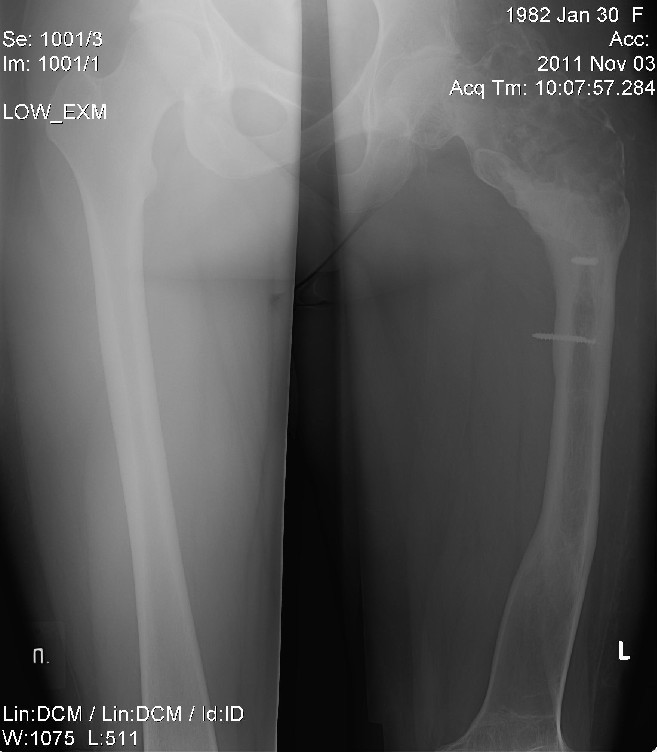

КТ от 2011 года.

КТ в/3 левого бедра по программе 2/2-10/10 с высоким разрешением: Отмечается увеличение в объеме («вздутие») метаэпифиза бедренной кости с истончением, а на отдельных участках с разрушением, замыкательной пластинки, неравномерный склероз диафиза с наличием единичных кистовидных просветлений.Определяется 2 инородных тела в в/3 диафиза – остатки винтов.Мягкие ткани с рубцовыми изменениями. Четких признаков воспалительной инфильтрации не отмечается.Существенной Ro динамики не выявлено.

Заключение: По совокупности данных можно думать о хр. Остеомиелите. Для диф. Диагностики с неопластическим процессом рекомендуется гистологическое исследование.